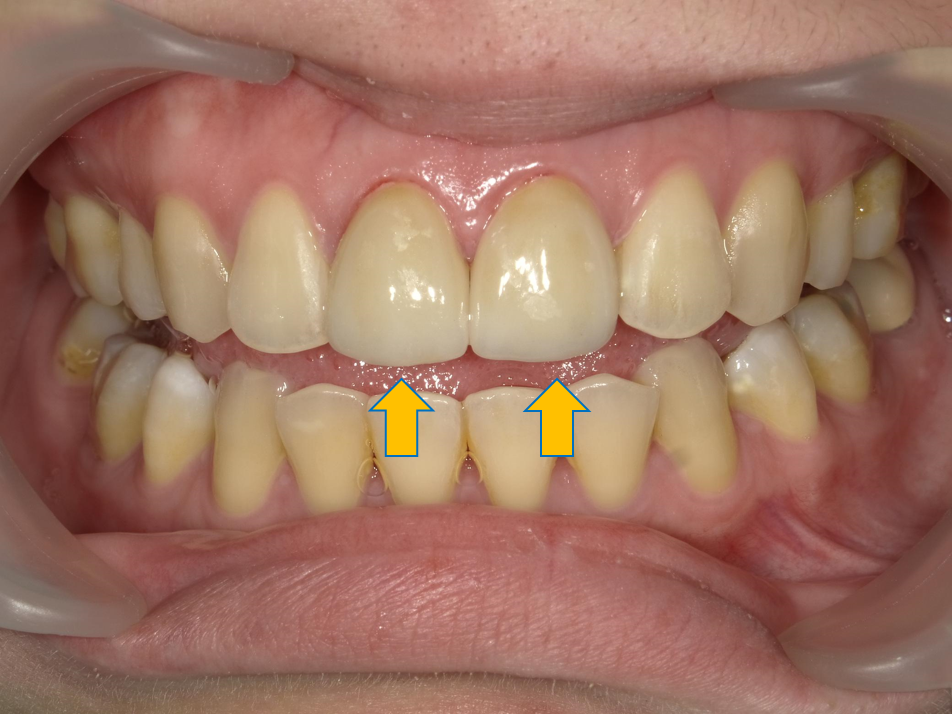

案例 1 術後(After)

門牙重建,改善咬合問題